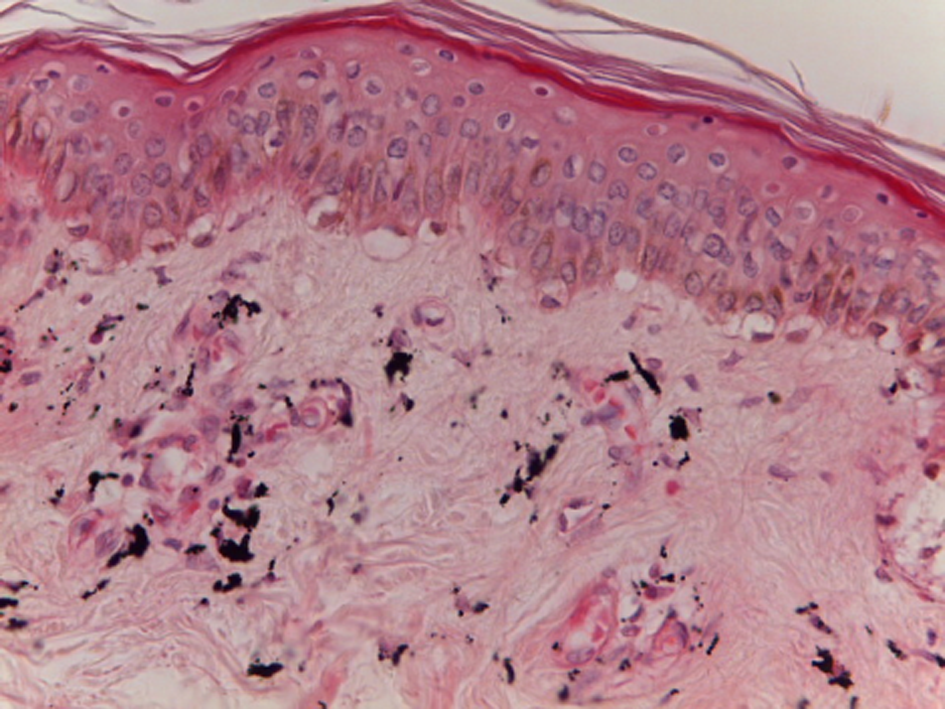

When performing the histological block of the study of the rats’ skin samples, it was found out that on the 3rd day, in the rats of the intact group, the skin was represented by two layers: epidermis and derma. The epidermis included horny, prickle-cell and basal layers adjacent to the basement membrane; the derma consisted of papillary and reticular layers (Fig. 2).